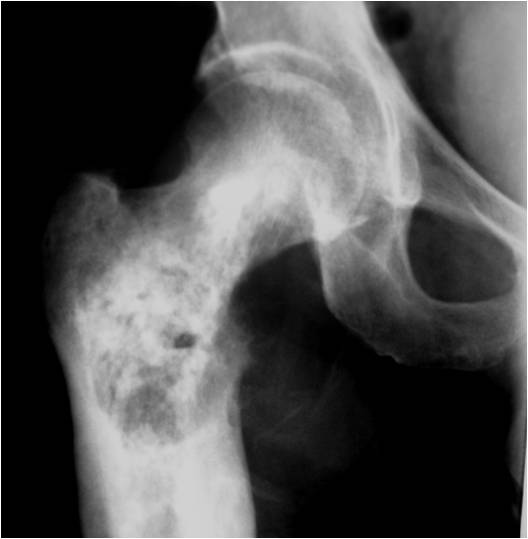

Radiographic Presentation

Radiology emulates pathology: Biphasic Tumor

- One region low grade chondrosarcoma

- Second more aggressive area with bone destruction, lysis of calcification, soft tissue mass

- Cortical permeation and a soft tissue mass in 70% of cases

Ill-defined, lytic intraosseous lesion

- Or extraosseous soft tissue mass

- Devoid of calcifications in continuity with lesions having the features of a cartilaginous tumor

Characteristically abrupt transition between chondroid tumor and dedifferentiated, lytic component

Bone may be expanded and adjacent cortex thickened

(Right Arrow)Aggressive Lytic Area (Dedifferentiated Sarcomatous Component) Cortical Destruction Soft Tissue Mass without Calcification